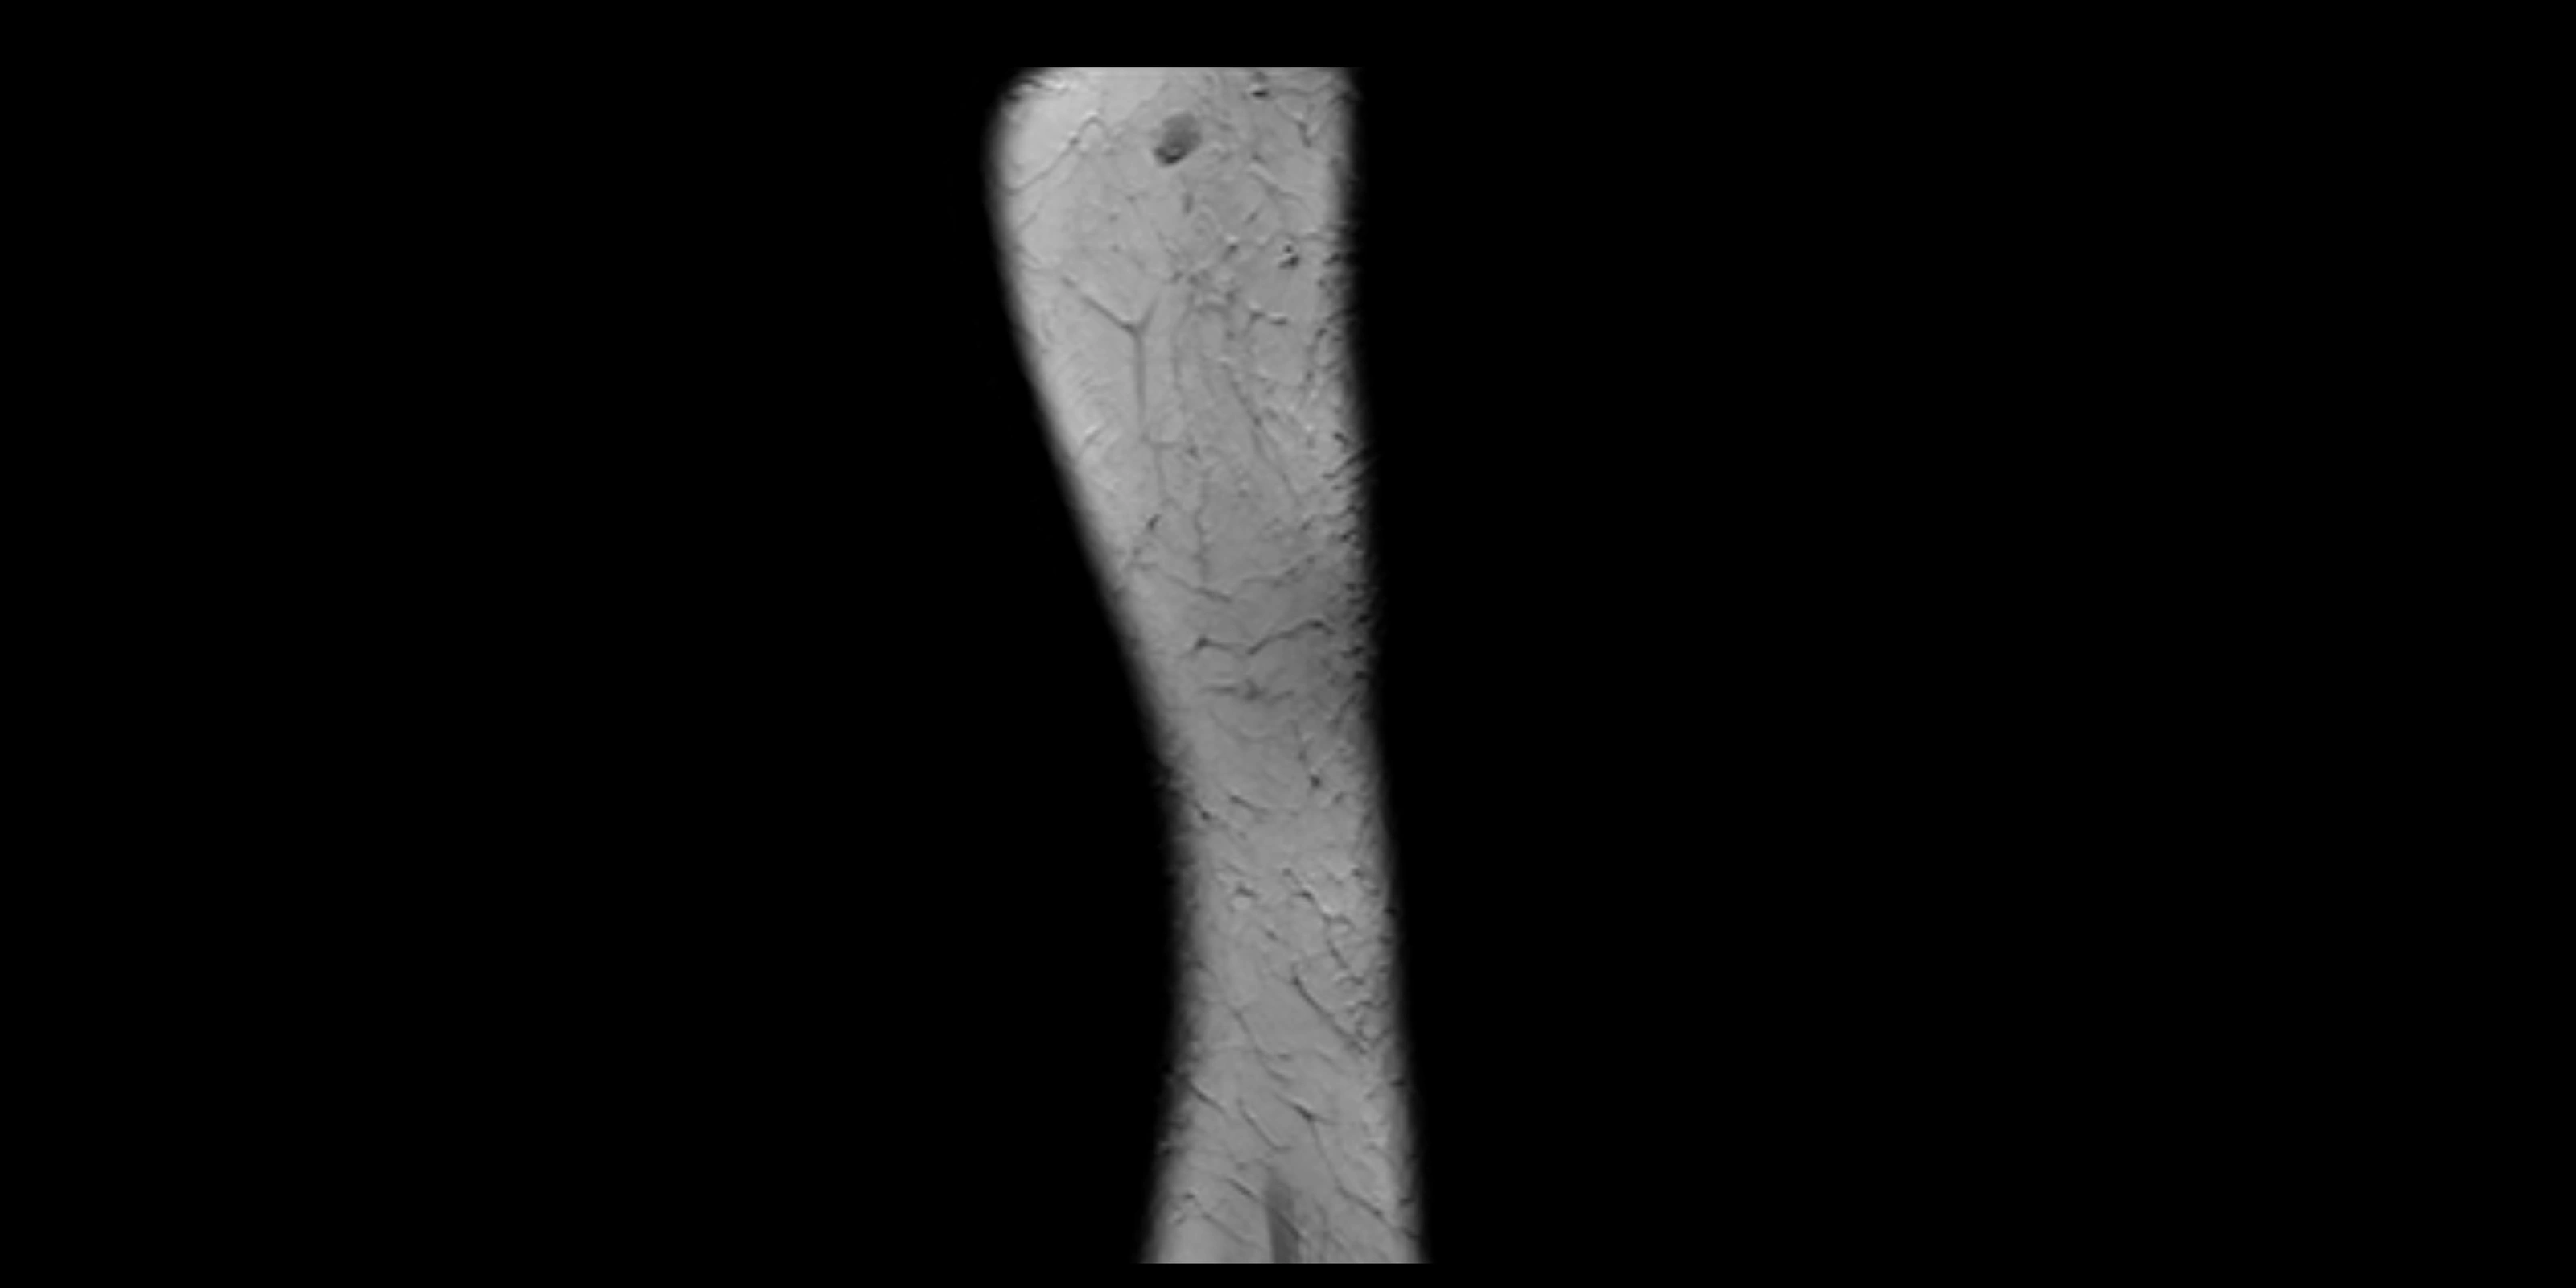

MRI images

image